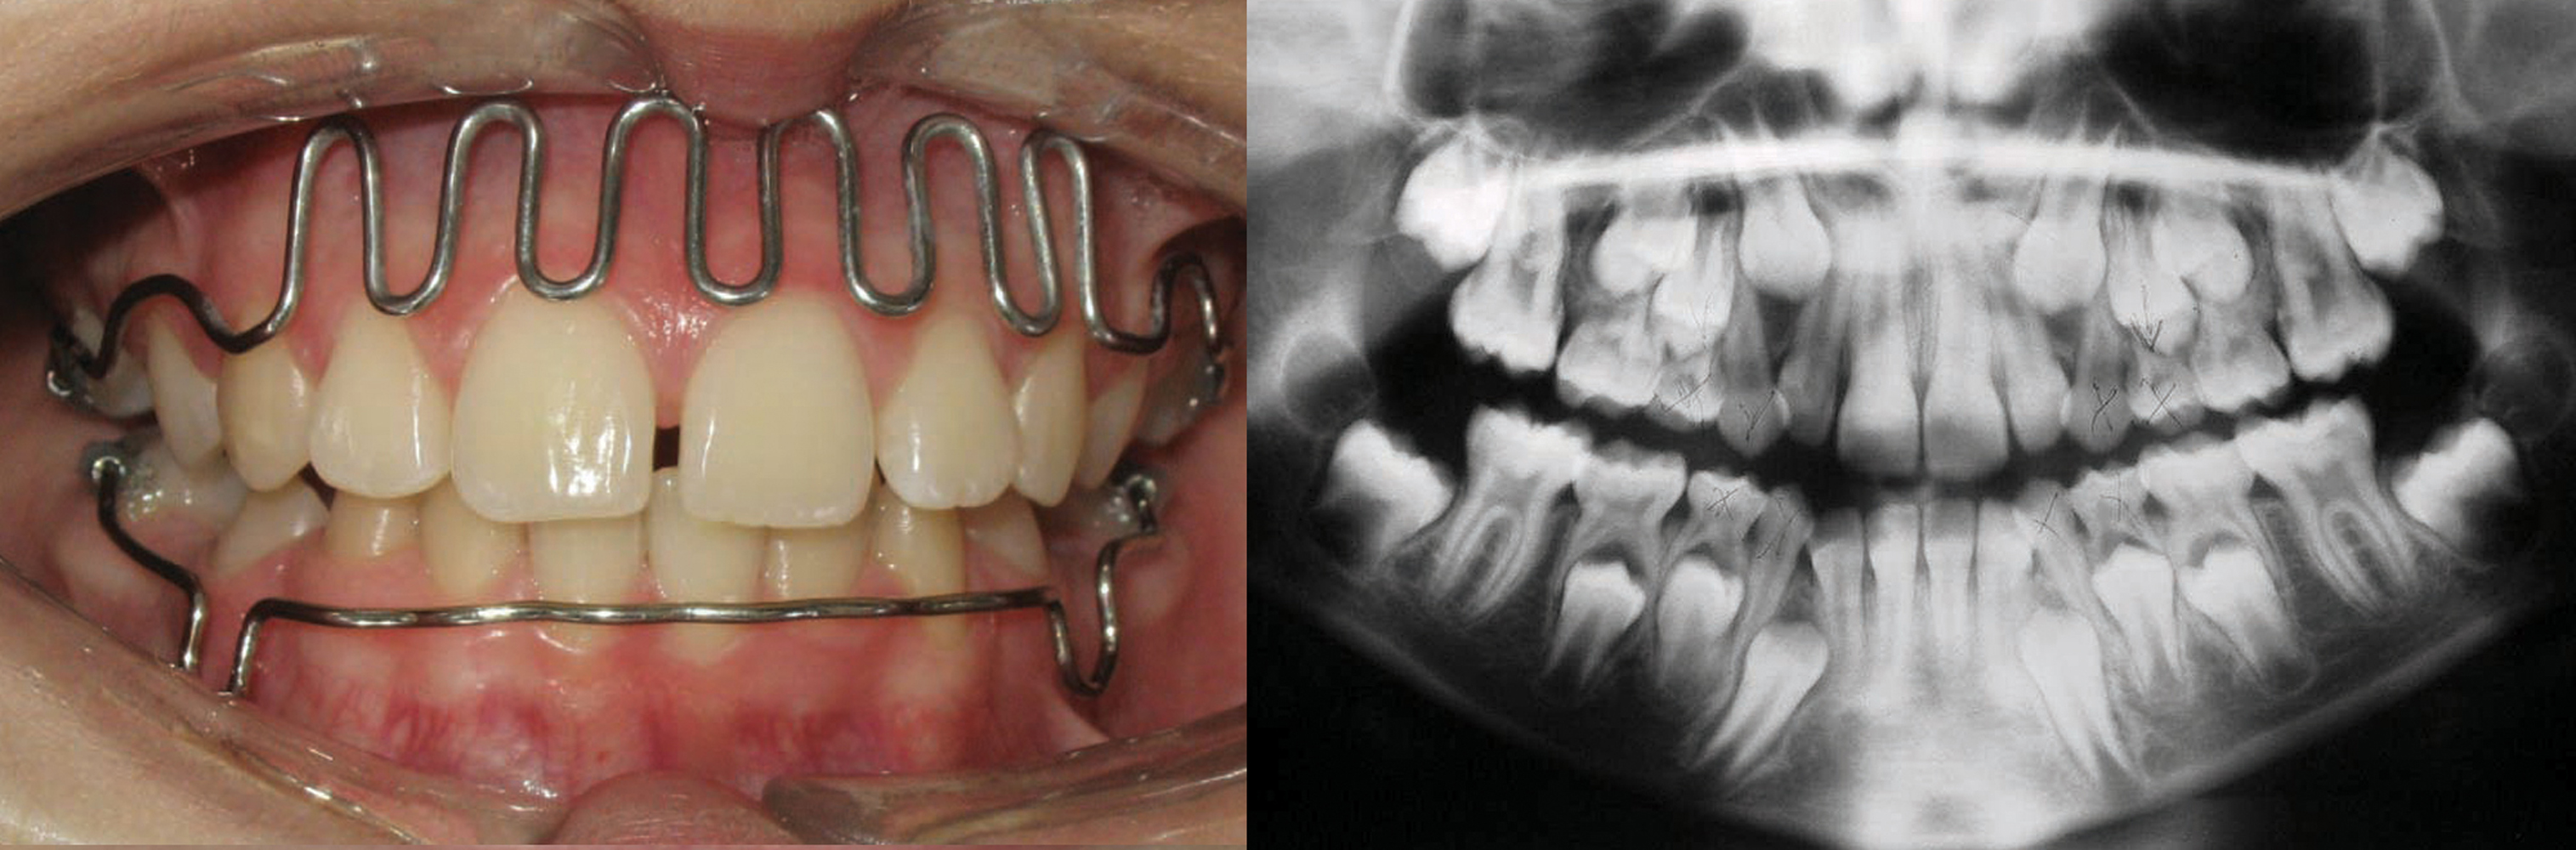

El propósito es presentar una propuesta clínica de intervención en niños basado en la experiencia de ocho años de aplicación piloto de terapias ortodóncicas tempranas en la Universidad de la Frontera en los pacientes de los alumnos de cuarto y quinto año de la Carrera de Odontología, así en consultorios de la región del sur de Chile. Se describen las bases para un adecuado diagnóstico y posterior tratamiento de anomalías frecuentes en niños, así como el desarrollo de la aparatología utilizada. En primer lugar el manejo de malos hábitos en pacientes clase II, luego la tracción frontal en pacientes clase III y finalmente el manejo del recambio en pacientes clase I. Aquellos pacientes que utilizan de buena manera sus aparatos obtienen resultados espectaculares. Por lo que la relación con los padres y la motivación a los niños son elementos fundamentales a la hora de decidir tratar a un niño con entrenadores, máscara de tracción o mantenedores de espacio dinámicos. A pesar de que no evita en todos los pacientes los tratamientos de ortodoncia correctiva, se mejoran las condiciones de los tejidos para una futura intervención de los especialistas. La dificultad encontrada en los servicios asistenciales en la aplicación de Ortodoncia temprana, contrasta con las políticas públicas de atención infantil que promueven una atención preventiva e interceptiva. Sin embargo la incorporación de aparatos prefabricados puede permitir el aumento de la cobertura, siempre y cuando los odontólogos que atienden niños comprendan su alcance y limitaciones.